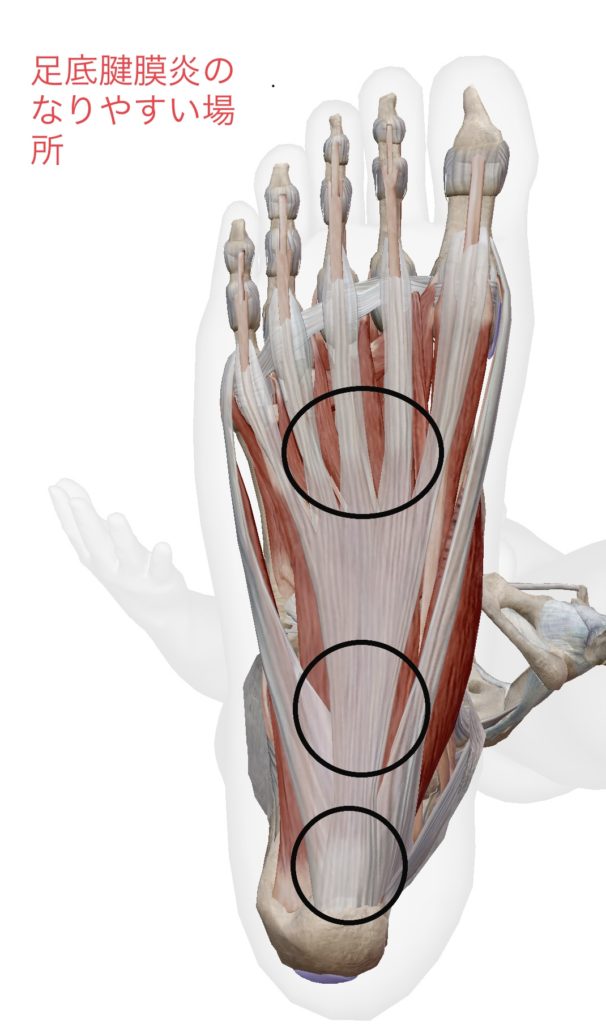

スポーツ選手や立ち仕事、よく歩く走る方に多く発症し足の裏に長時間の負担がかかり続けると、踵の裏を中心に足の全体が痛くなり炎症が起こります。